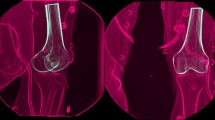

The data were collected using a radiographic setup for dynamic RSA. The device used (BI-STAND DRX 2) was developed in our institute, in collaboration with ASSING (ASSING Group, Rome, Italy). The specifics of the RSA radiographic setup were analogous to the ones already published in previous articles from the same study group [3, 4] (Fig. 1a).

Radiological setup of the RSA device, where patients performed motor tasks. The orthogonal arrangement of flat panels and X-ray tubes allows a 3D reconstruction of bone movements (a); virtual reconstruction of a motor task in the RSA software, where mathematical data describing tibio-femoral kinematics were extrapolated (b)

Bone models of tibia and femur were obtained from a 1.5 T MRI of either the affected or the contralateral knee. When MRI images of the contralateral knees were not available, the models were derived from a process of mirroring of the ones of the affected knee and of their correspondent reference systems. The radiographic images were processed in a dedicated software in Matlab® (R2016a, MathWorks Inc., Natik, MA, USA) developed at our institute, applying algorithms related to the Model-Based Dynamic RSA. A 3D virtual environment was used for semi-automatic segmentation of bone contours on radiographic images and, subsequently, to place the bone models according to the contours (Fig. 1b).